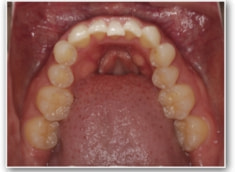

叢生+左下1番先天欠如ケース

治療前